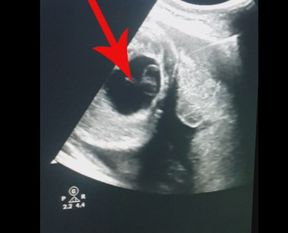

Konya'da 30 haftalık kız bebeğin anne karnındayken gerçekleştirilen cerrahi operasyonla yumurtalık kisti alındı.

Çapar, hamileliğin 30. haftasında anne karnındaki bebek için ameliyat kararı aldı. Gerçekleştirilen cerrahi operasyonla bebekteki 6 santimetre civarındaki yumurtalık kisti başarılı şekilde alındı.

Operasyonla ilgili AA muhabirine bilgi veren Prof. Dr. Metin Çapar, hastalarının normal gebelik kontrolleri sırasında anne karnındaki kız bebekte yumurtalık kisti tespit ettiklerini söyledi.